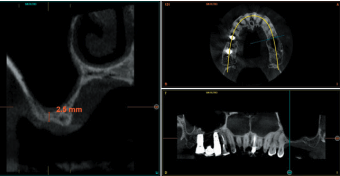

Todos los pacientes fueron tratados por un mismo cirujano, para la realización de la inserción de los implantes y la técnica de elevación transcrestal. Antes de la inserción de los implantes se utilizó una premedicación antibiótica consistente en amoxicilina 2gr vía oral una hora antes de la intervención y paracetamol 1 gramo vía oral (como analgésico). Posteriormente los pacientes prosiguieron con un tratamiento de amoxicilina 500-750 mg vía oral cada 8 horas (según peso) durante 5 días. Todos los pacientes fueron estudiados antes de la inserción de los implantes mediante modelos diagnósticos, exploración intraoral y realización de una tomografía computerizada de haz cónico (CBCT), analizado posteriormente mediante un software específico (BTI-Scan III). La cirugía se lleva a cabo mediante la técnica de fresado biológico descrita por nuestro grupo de estudio previamente, a bajas revoluciones, sin irrigación10, hasta ser finalmente completada mediante la elevación transcrestal con las fresas de corte frontal que se emplean también a bajas revoluciones. Una vez la membrana es accesible mediante la perforación crestal se despega mediante una ligera presión y se inserta el implante con el motor quirúrgico fijado a 25 Ncm y 25 rpm finalizando la inserción del implante con la llave dinamométrica. Todo el hueso recogido con las fresas se conserva en PRGF-Endoret fracción 2 sin activar, para posteriormente ser utilizado como injerto óseo particulado en la elevación, sin otros materiales accesorios9,12. Una vez finalizada la cirugía se realiza una radiografía periapical con paralelizador que será la que se utilice como punto de partida. Los pacientes acuden posteriormente para la realización de radiografías periapicales de control, tomadas con la misma técnica y sobre estas radiografías se realizan las mediciones necesarias para comprobar la estabilidad y pérdida ósea crestal de los implantes. La medición de la pérdida ósea marginal se realizó en la última radiografía periapical realizada con posicionador de seguimiento.

En la Figura 2 se muestran los diámetros y longitudes de los implantes incluidos en el estudio en función de los milímetros de cresta ósea residual en altura. La densitometría media de la zona de inserción del implante del grupo fue de 293,33 HU (+/- 144,99). El torque medio de los implantes estudiados fue de 27,33 Ncm (+/- 16,99). Todos los implantes se cargaron en dos fases quirúrgicas y en todos se llevó a cabo una elevación de seno transcrestal con injerto óseo autólogo particulado obtenido del fresado, embebido en PRGF-Endoret como marterial de injerto. En ninguno de los casos se registraron complicaciones relativas a la cirugía. Los implantes presentaron un seguimiento medio de 13,33 meses tras la carga (+/- 3,09), no encontrándose complicaciones ni fracasos durante este tiempo de seguimiento, por lo que la supervivencia fue del 100%. Todos los implantes fueron rehabilitados mediante prótesis múltiple atornillada mediante elemento intermedio (transepitelial múltiple, Multi-im®), encontrándose dos de los implantes ferulizados a otros de la misma longitud (4,5 mm) y el resto a longitudes mayores. La ratio corona-implante medio para el grupo de estudio fue de 2,43 mm (+/-0,45). La pérdida ósea mesial final media de todos los implantes fue de 0,42 mm (+/- 0,51) y la pérdida ósea distal final media de 0,16 mm (+/-0,34). En las Figuras 3 –13 se muestra uno de los casos incluidos en el estudio.